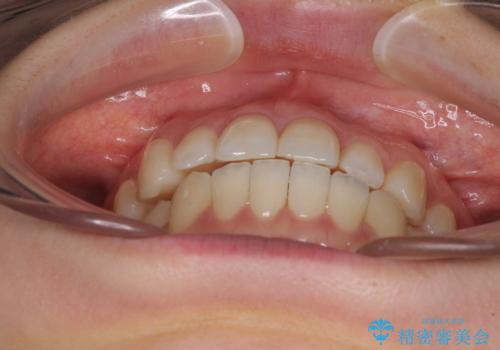

前歯のクロスバイト インビザラインによる矯正治療

- 前歯のクロスバイトを気にして来院された患者様です。

短期間での治療を希望され、ワイヤー装置とインビザラインとで悩んでいましたが、自己管理を徹底すると言うことでインビザラインによる矯正治療を行うこととしました。

しっかりとインビザラインの装着時間を守っていただいたので、1年弱で矯正治療を終えることができました。